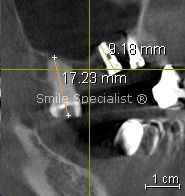

The closest replacement for natural teeth. Even in cases with reduced bone, Specialist planning can often produce successful outcomes.

Smile Specialist Centre's Implants in reduced bone Implant carrying crown Measuring bone in 3D imaging Smile Specialist Centre